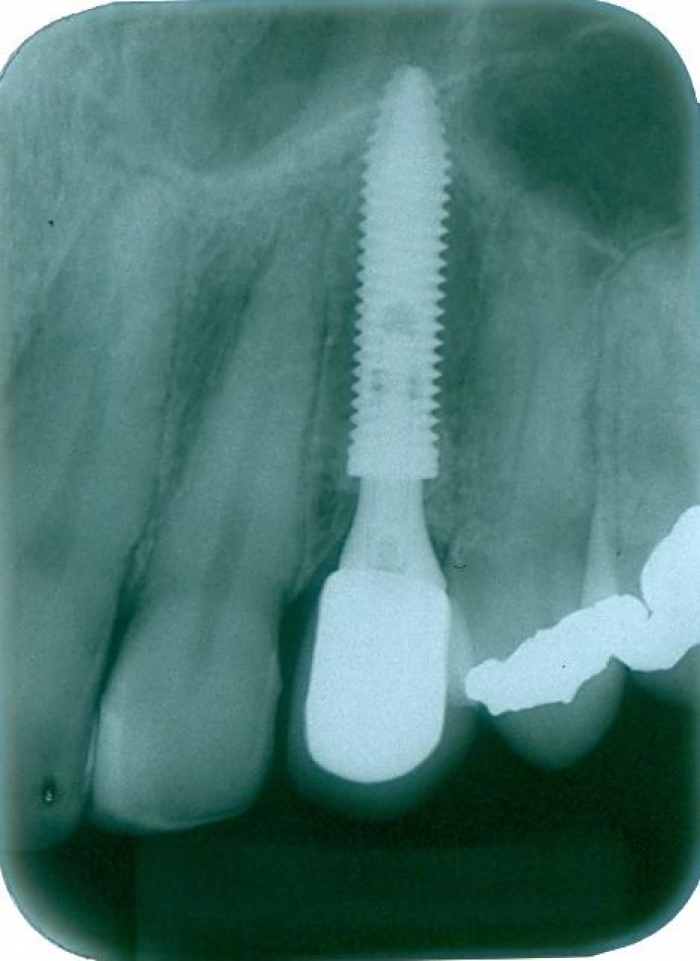

Raio X após mesialização da raiz do dente 22

Raio X após a extração e implante imediato